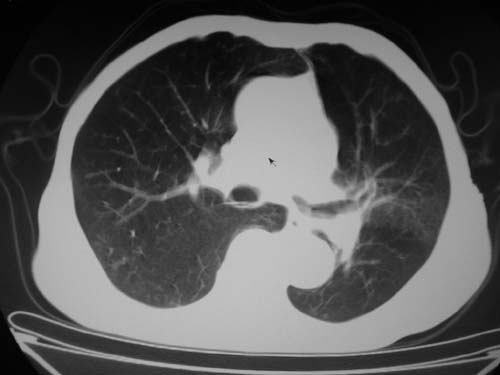

标题: CT19736:男,76岁,咳嗽,胸痛 [打印本页]

标题: CT19736:男,76岁,咳嗽,胸痛

支持左上肺周围型肺癌性并空洞形成伴胸椎转移。

支持左上肺周围型肺癌并空洞形成伴胸椎转移。z左下肺炎

左上肺癌性空洞伴胸椎转移。